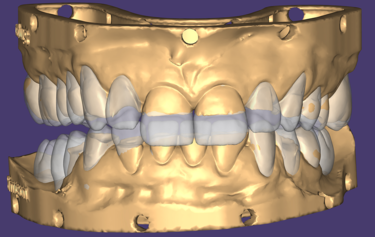

Figure 14: Final full mouth digital restoration designs

On receiving the scans of the final tooth preparations, the laboratory was able to overlay the planned final restorations which the milled temporaries had been based upon. The small modifications to the occlusion which was completed at the earlier temporary stage could be adapted into the digital design, and then the individual restorations adapted to the refined finishing margins of the final tooth preparations (Fig. 14). The final restorations were then milled in IPS e.max ZirCAD Prime Esthetic in the lighter BL4 shade using the PrograMill PM7 milling unit. New working models were 3D-printed of the preparations, and a second set of oversized models were made to compensate for the increased size of the pre-sintered Zirconia (Fig.15). The larger model was scaled up to match the shrinkage factor of the zirconia to allow the restorations to be checked on the oversized model. This additional check stage allows for assessment of marginal fit and contact areas, in addition to checking the passivity of fit and the occlusion, ahead of sintering.

The patient returned after two weeks, and the final restorations were once again assessed. All margins, occlusion and excursions were re-checked and there were no further adjustments necessary (Fig. 24 & 25). Note the beautiful tooth morphology and the detailed surface texture that is achievable with modern digitally designed tooth libraries and state-of-the-art milling machines. The transfer of digital design to final restoration is an exact replication and this can be seen on the comparison of digital overlay against the final zirconia restorations in Figure 26

By approaching multiple restorations in the same methodical and planned approach every time, the SmileFast protocol, integrated with a digital ceramic workflow, guarantees predictable and consistently excellent aesthetic results. Figure 6 and 26 show the restored upper arch with composite (Fig. 6) and ceramics (Fig. 26) in direct comparison to the planned digital design; the accuracy of transfer is very precise, with the natural texture and the detailed morphology being replicated exactly.